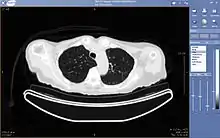

An image as stored on a picture archiving and communication system (PACS)

The same image following contrast adjustment, sharpening and measurement tags added by the system